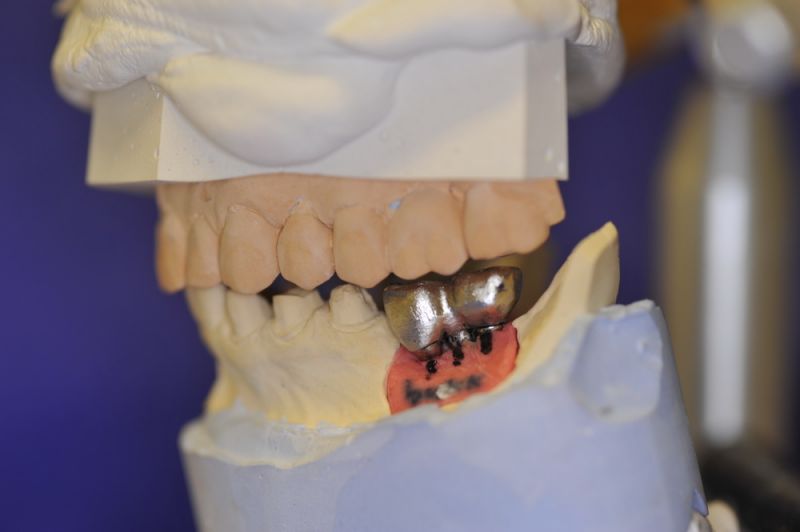

Es war eine Kombination aus Schmerzen bis an die Suizidgrenze, beschränkten wirtschaftlichen Möglichkeiten, sehr stark eingeschränkten Möglichkeiten der für Implantate zur Verfügung stehenden Knochenverhältnisse in einem stark atrophierten Unterkieferseitenzahnbereich und zudem dann auch noch durch auftretenden Problemen bei der Implantatinsertion und nachfolgenden Versorgung der Implantate.

Die Problematik der Implantatversorgungen kann man in einer Analogie folgendermaßen darstellen. Die räumlich beengten Zustände gleichen dem Tanz eines Paares auf einer Briefmarke, und der gleichzeitigen Schritt- und Fusshaltung, dass beim Tanzen die Schuhe geputzt werden können!